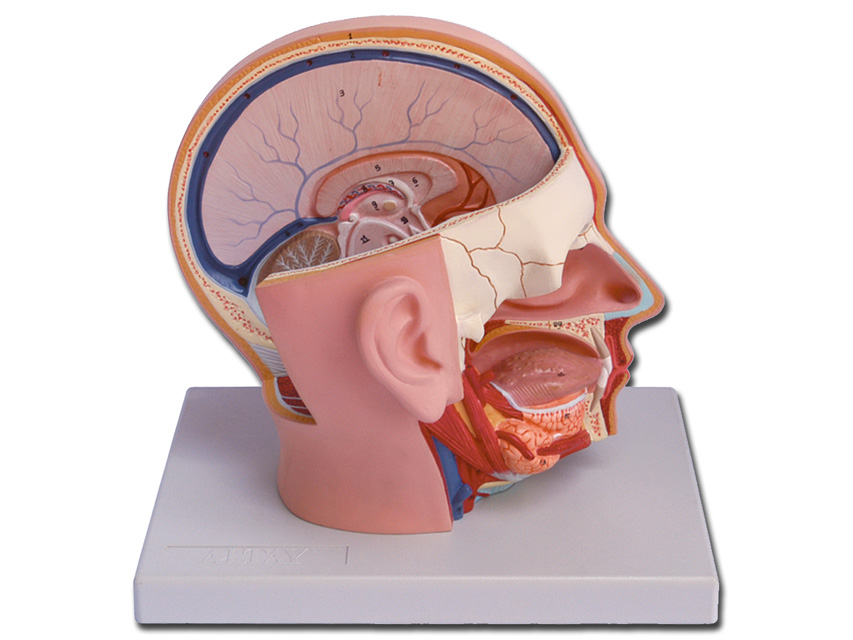

MODELLO TESTA - 4 parti - 1X

Modellino anatomico di dimensioni reali composto da 4 parti, come segue:

- Metà cervello, mostra la struttura interna del cerebrum e i relativi vasi sanguigni

- Metà cerebellum

- Occhio con nervo ottico

Il lato destro della faccia è sezionato lungo la linea orizzontale e sagittale. Questo modellino anatomico molti dettagli significativi del cervello a del cranio assieme all'intera cavità oro-nasale. • Dimensioni: 18 x 25 x h 23 cm

• Parti: 4

• Ingrandimento: 1X